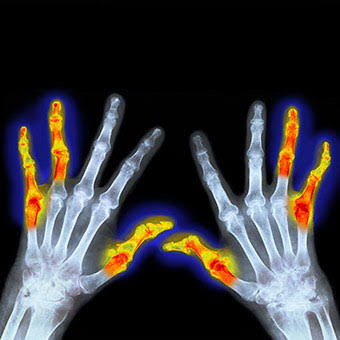

类风湿关节炎,其主要的病理基础是滑膜的改变,当滑膜出现了类风湿滑膜炎改变以后,会逐渐的破坏掉关节腔内的软骨,导致关节间隙的狭窄和关节的粘连,严重的影响患者的生活质量,很多人因为手部的变形甚至筷子都拿不了。

类风湿性关节炎的患者早期通常会表现出明显的晨僵,尤其是表现在手部。很多患者会在早期的时候表现出早上起来的时候,手指的僵硬感,握不拢,而且握拳的时候会有疼痛,通常需要经过30分钟左右的时间才能缓解。

当然当很多患者已经到了晚期,关节已经出现了明显的变形,从相关的查体以及x光片子,也可以明确患者是否存在类风湿性的关节炎。从下图您仔细看就会看出正常的手与类风湿性关节炎手部的骨骼改变。